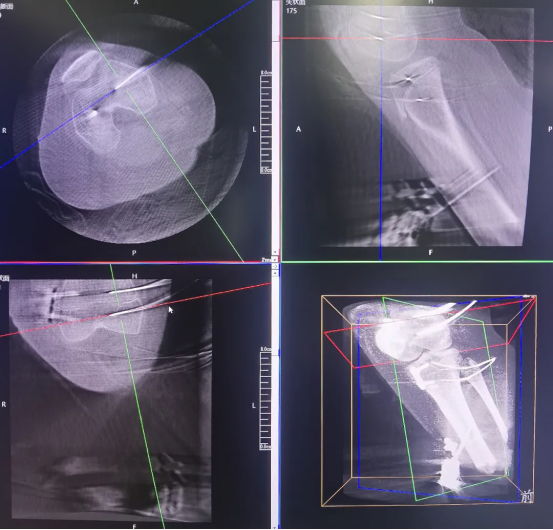

After screw placement, it is necessary to confirm whether their positions meet biomechanical requirements, as this directly affects the effectiveness of postoperative growth inhibition and the safety of skeletal development. Traditional 2D fluoroscopy cannot fully assess the screws’ positions in three-dimensional space, making it easy to overlook subtle deviations.

Perlove Medical’s 3D C-arm performs postoperative scans to verify screw placement from multiple dimensions: the relationship between the screws and the epiphyseal line

, any loosening or displacement and whether the femoral and tibial mechanical axes are approaching balance. If any subtle issues are detected, timely adjustments can be made to ensure optimal screw fixation. This postoperative 3D verification eliminates the observation blind spots in 2D imaging and serves as the final safeguard for surgical outcomes and long-term skeletal health.